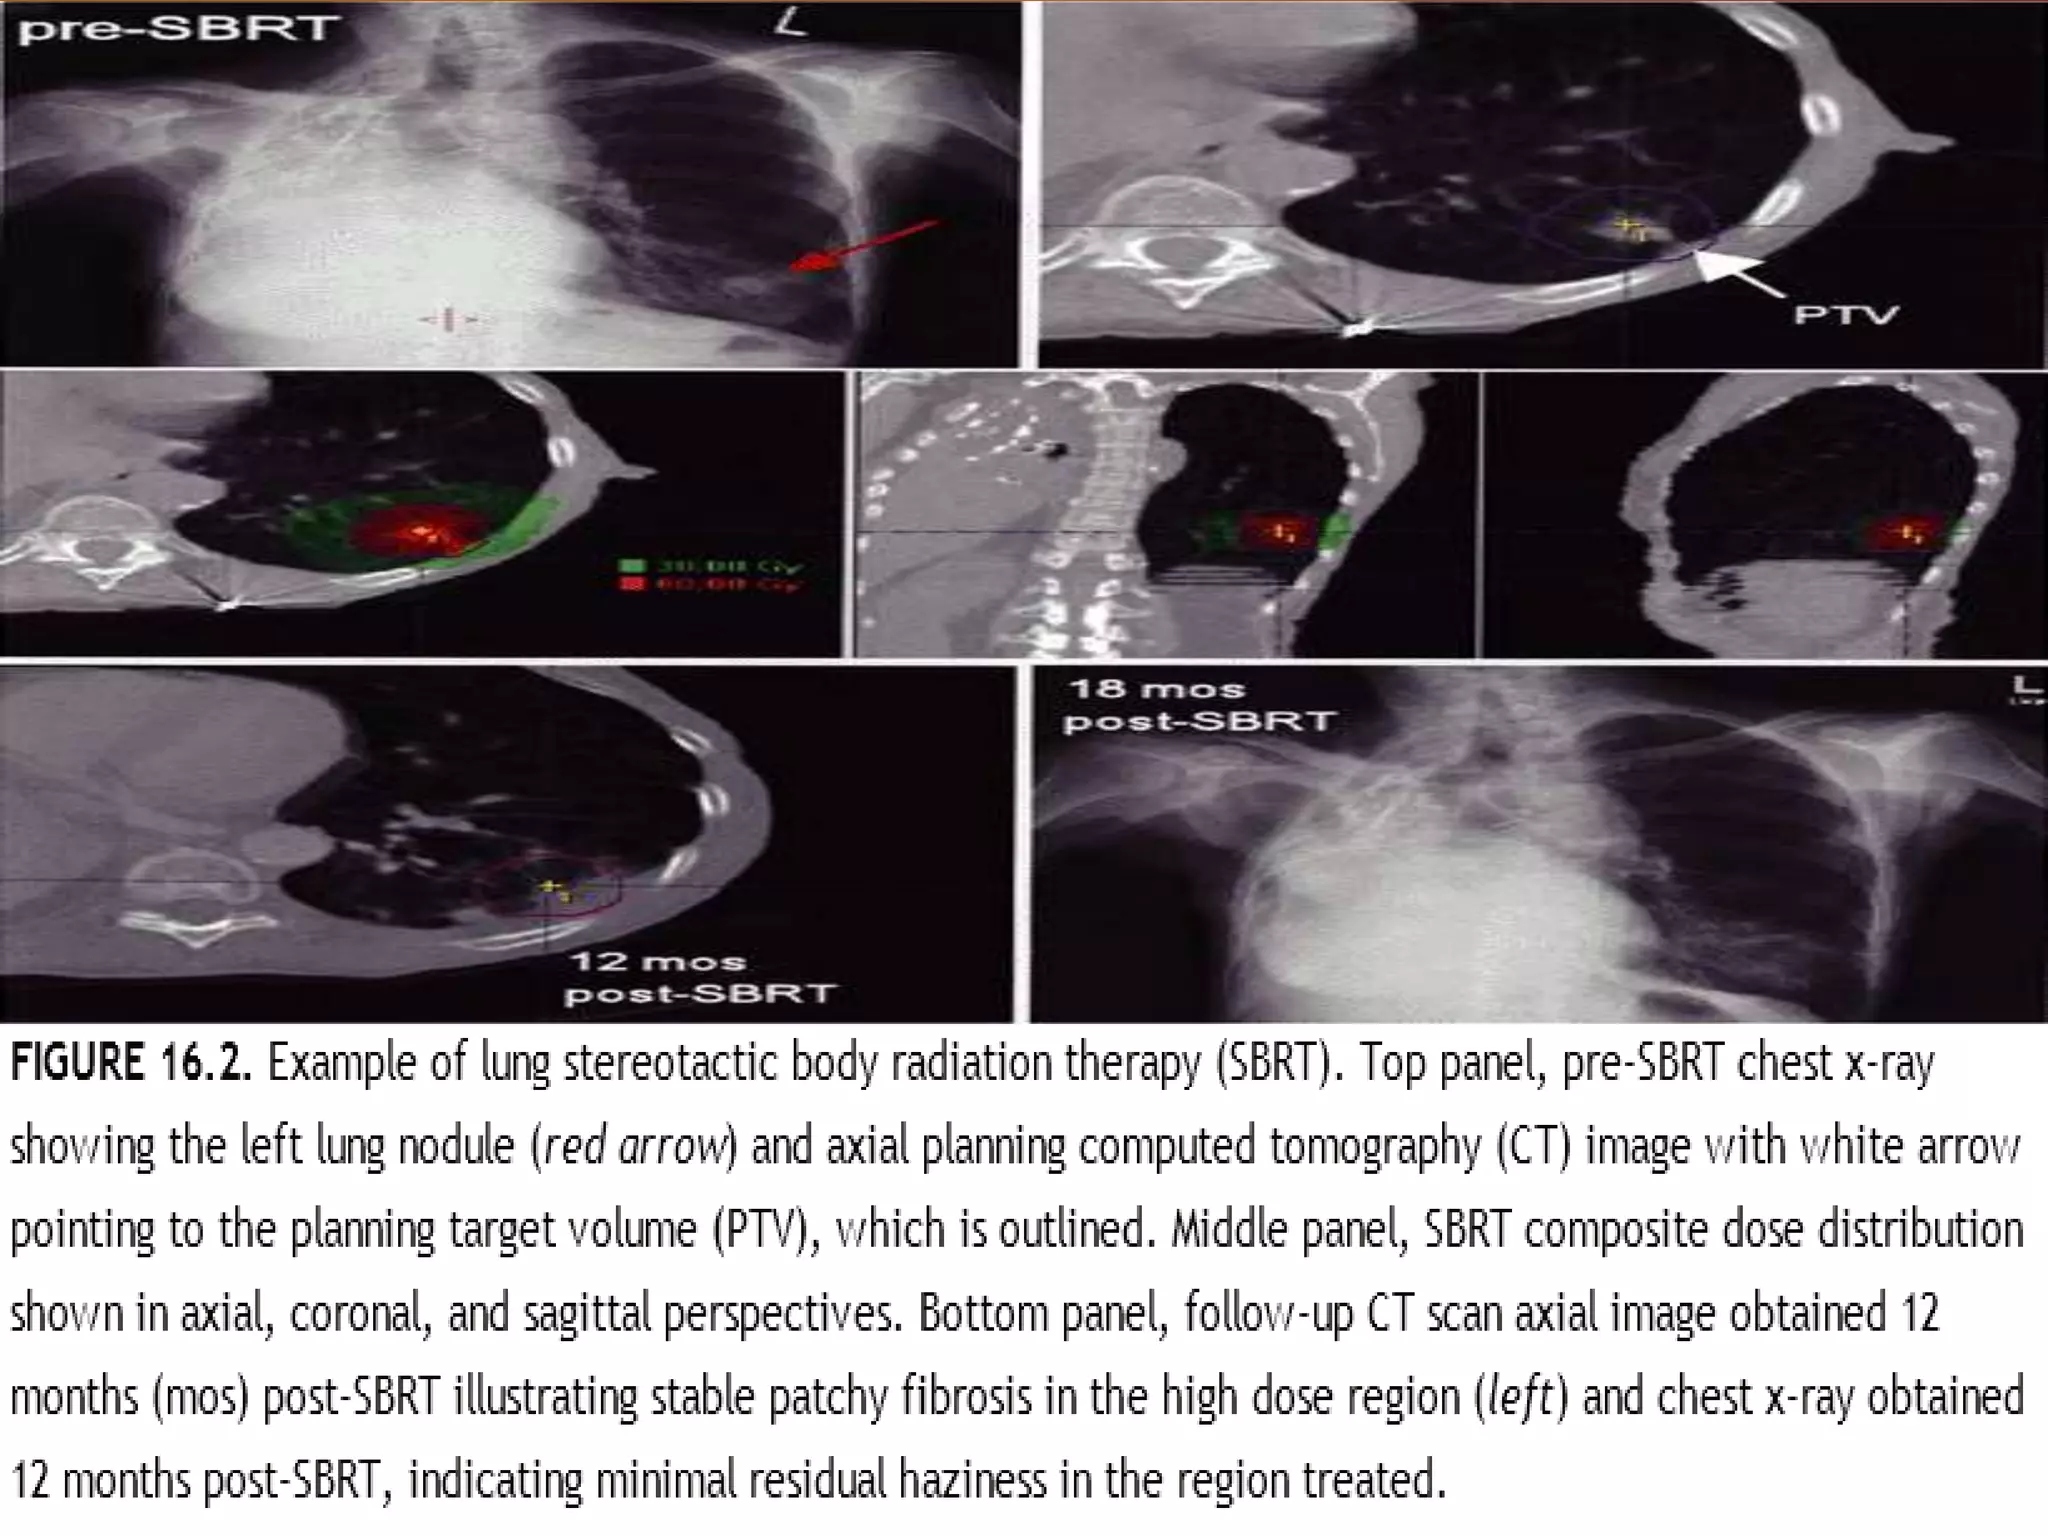

Several institutions have studied stereotactic body radiation therapy (SBRT) for primary lung cancer. Indiana University studies showed a maximum tolerated dose of 66 Gy for T2 lesions delivered over 3 fractions, with 1-year local control rates of 98%. Other studies from Aarhus University, Kyoto University, Air Force General Hospital in Beijing, and University of Marburg demonstrated 1-2 year local control rates ranging from 85-95% using SBRT dose fractions between 30-60 Gy delivered over 1 to 10 fractions.